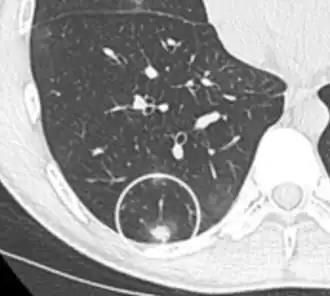

- Pleural retraction is far more common in cancers.[9] It is the pulling of visceral pleura towards the nodule.[9]

Nodule with pleural retraction.[9] -

In this case, pleural retraction is seen as a triangular fat component.[9]